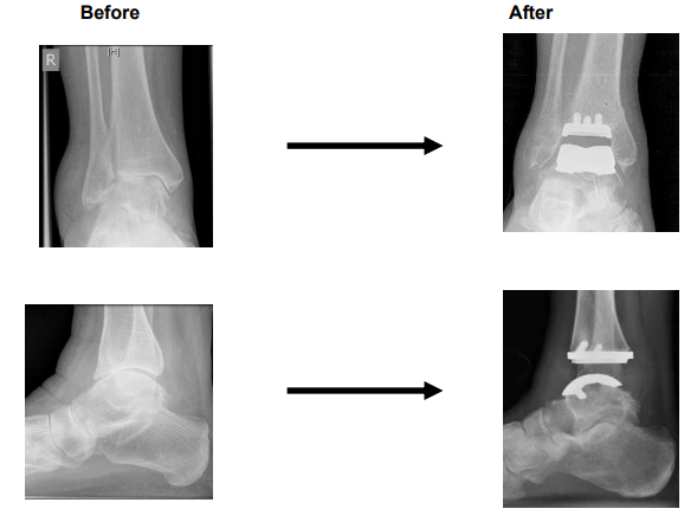

A total ankle replacement involves taking out the worn-out ends of your tibia and talus bones (two bones that form the main hinge in your ankle) and replacing them with artificial ends made from metal with a plastic insert. This is called a prosthesis.

Unlike an ankle fusion, a replacement allows you to move your joint after surgery.

Appearance on X-ray before and after the surgery